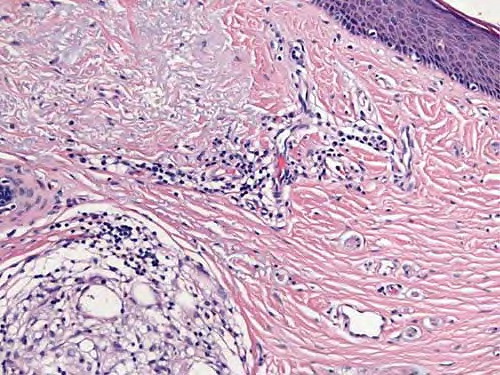

Surgical scar = ندبة جراحية